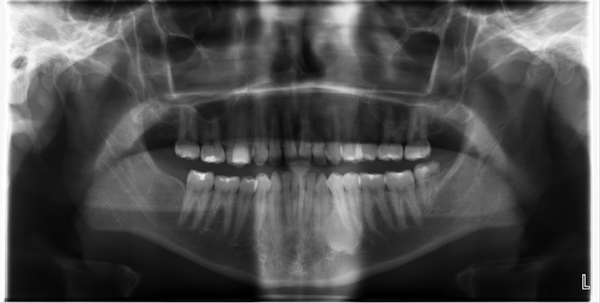

DEFINISIPesawat dental x-ray panoramic adalah suatu peralatan di bidang radiologi yang digunakan untuk menangkap seluruh bagian mulut dalam suatu gambar termasuk gigi ata dan rahang bawah struktur dan jaringan sekitarnya dengan menggunakan sinar-x. Rontgen gigi juga disebut dengan radiografi gigi atau sinar X gigi. Rontgen gigi atau dental X-ray adalah prosedur medis untuk mengambil gambar bagian dalam mulut menggunakan cairan radiasi. Indirect conversion is so named because this technique still uses a scintillator to convert x. 11-32 A-C the PA does not show the transported canal and extent of short fill which is more evident in the CBCT.

Dental X-ray unit merupakan suatu alat yang memanfaatkan perubahan energi listrik menjadi sinar-X dan panas. X-ray viewer ini berguna untuk dokter membaca hasil x-ray scan terhadap gigi dan mulut pasien yang nantinya digunakan sebagai acuan untuk tahap atau perawatan yang akan diberikan kepada pasien. DIRECT DIGITAL RADIOGRAPHY Agus Komarudin ST MT. Rontgen gigi juga disebut dengan radiografi gigi atau sinar X gigi. Peralatan Radiologi III Hertia Rusli P23138114041 Iqbal Dwipermana Jaja P23138114045 Ivan Kurnia Juliandri P23138114047 POLITEKNIK KESEHATAN KEMENKES JAKARTA II JURUSAN TEKNIK ELEKTROMEDIK JlHang Jebat IIIF3 Kebayoran BaruJakarta Selatan 12120 Telp021-7243687 Fax 021-7261723 Website.

Anatomi dan Fisiologi Gigi. Smyrna DE 19977 directions 302-659-4401 Services are by appointment unless otherwise noted. MANFAAT PEMERIKSAAN DENTAL RADIOGRAPHY. Anatomi dan Fisiologi Gigi. CTCTA Monday Friday 8 am.